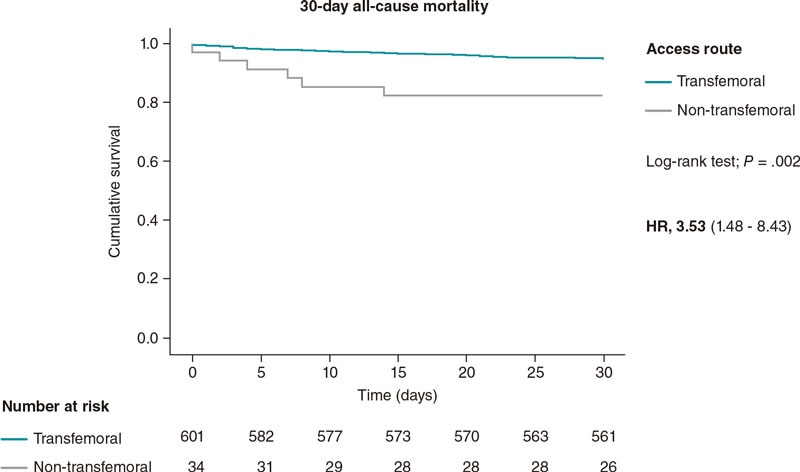

Predilatation occurred in 32 lesions (51.6%) and postdilatation in 37 (59.7%). The criterion used for postdilatation was angiography guided visual underexpansion. Intravascular ultrasound was performed in 15 patients (30%) before the implant. It was also used in 2 patients to optimize the percutaneous coronary intervention given the persistent stent underexpansion seen on the angiography. In both cases the minimum lumen area was > 5.5 mm2 with stent expansion > 80% and lack of incomplete apposition (defined as a strut separation of > 0.4 mm axial and 1 mm longitudinal) (figure 2). The optical coherence tomography was performed in a patient with ST-segment elevation acute coronary syndrome before and after the implant. It revealed a high thrombotic load with lack of immediate stent malapposition.

Figure 2. A: acute thrombotic occlusion in left circumflex artery with Thrombolysis in Myocardial Infarction flow grade 0. B: the intravascular ultrasound shows a great deal of thrombus in the lesions despite thrombus aspiration. C: implantation of 2 3.5-4.5 mm × 27 mm Xposition S overlapping stents. D: the intravascular ultrasound performed after stent implantation confirms the good angiographic results and lack of stent malapposition.